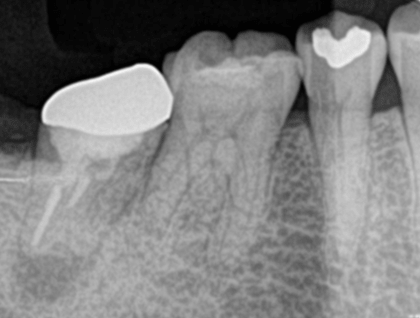

症例3【40代女性】右上74根尖病巣の治療 右上56 洞低膜を挙上しインプラント埋入

治療前

治療後(5年経過)

主訴 右上で物が噛めない。インプラントを希望され来院。

右上第二小臼歯はC₄にて抜歯。右上第一大臼歯は欠損の状態。

残存骨が5~6㎜程で、インプラント埋入には骨の高さが不足している為、ソケットリフト(骨造成)を行った。洞底膜を挙上することで、骨の高さの不足を解消。

採血のよるCGFメンブレンとAFGブロック(人工骨β‐TCPとAFGを混ぜたブロック)を填入しインプラント2本を埋入。約4ヶ月の免荷期間を経て、仮歯を装着、リハビリをし、約5ヶ月後にメタルボンド(金属焼付ポーセレン)を装着。

リスクとしては、ソケットリフト(骨造成)による一過性の副鼻腔炎が起きる可能性がある。まれに洞底膜が破れる可能性がある。ただし、膜は約3週で再生するので、膜の回復を待ち、再オペを行う。

費用 113万(オペ・ソケットリフト・人工骨・採血による濃縮血小板生成・仮歯・最終補綴物まで含む)